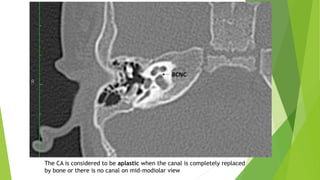

8- Cochlear Aperture

Abnormalities

Cochlear Aperture Abnormalities

The CA, cochlear fossette, or bony cochlear nerve canal transmits the

cochlear nerve from the cochlea to IAC.

The CA is considered hypoplastic if the width is less than 1.4 mm.

Hypoplastic bony canal for cochlear nerve (BCNC).

The CA is considered to be aplastic when the canal is completely replaced

by bone or there is no canal on mid-modiolar view

CA abnormalities may be accompanied by a narrow IAC on HRCT.